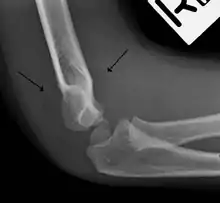

The fat pad sign, also known as the sail sign, is a potential finding on elbow radiography which suggests a fracture of one or more bones at the elbow. It is may indicate an occult fracture that is not directly visible. Its name derives from the fact that it has the shape of a spinnaker (sail).[1] It is caused by displacement of the fat pad around the elbow joint. Both anterior and posterior fat pad signs exist, and both can be found on the same X-ray.

In addition to fracture, any process resulting in an elbow joint effusion may also demonstrate an abnormal fat pad sign. Increased intracapsular fluid is also seen in several conditions other than fracture and this produces the abnormal fat pad sign. (toxic synovitis, septic arthritis, Juvenile Rheumatoid Arthritis, osteomyelitis of the distal humeral physis and secondary septic joint). In these instances, history and clinical examination in addition laboratory results (WBC, ESR, CRP) will guide the provider in determining whether to treat the condition as an occult fracture or continue workup for other pathology.

The posterior fat pad is normally pressed in the olecranon fossa by the triceps tendon, and hence invisible on lateral radiograph of the elbow.[3] When there is a fracture of the distal humerus, or other pathology involving the elbow joint, inflammation develops around the synovial membrane forcing the fat pad out of its normal physiologic resting place. This is visible as the "posterior fat pad sign" and is often the only visible marker of a fracture, particularly in the pediatrics population.